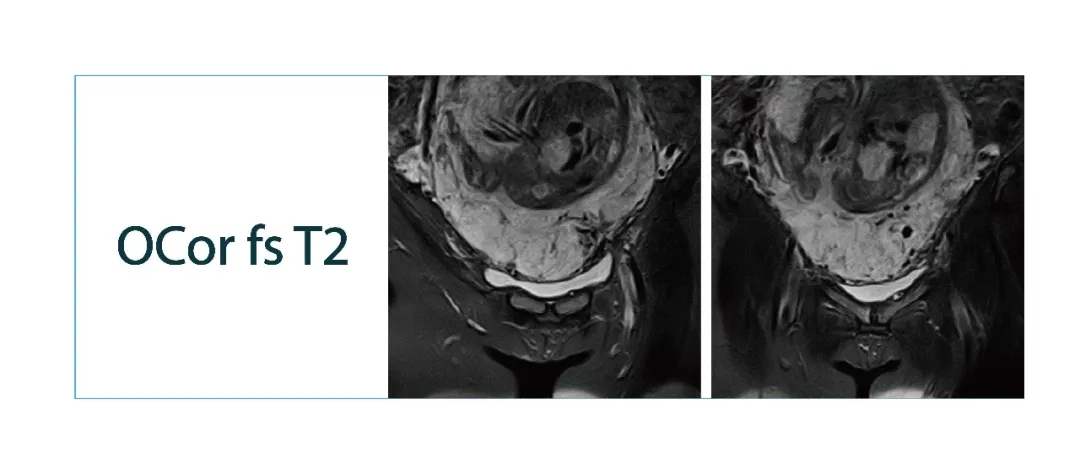

【朗润影像档案】20180302磁共振影像病例结果讨论